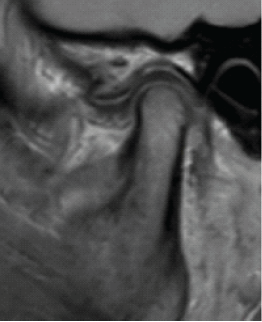

Magnetic Resonance Imaging Evaluation of Temporomandibular Joint Involvement in Ankylosing Spondylitis Patients

Rahul Srivastava , J Srilakshmi , Vinay Kumar , Sumit Bhatt , Sania Khan , Brijesh Byrappa

………………………………p.329-334